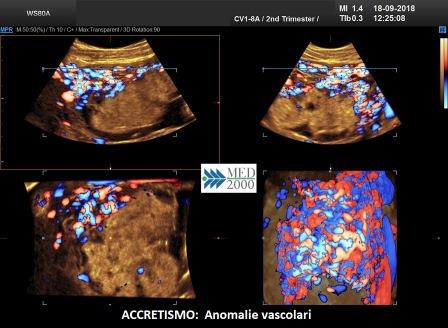

I Criteri ecografici possono essere distinti in:

criteri ecografici color doppler

- l'arcata vascolare normalmente parallela al piatto basale perde questa caratteristica

- presenza di lacune vascolari placentari con flusso turbolento (velocità di picco sistolico > 15 cm./sec.)

- vascolarizzazione intraplacentare irregolare con vasi tortuosi confluenti

- ipervascolarizzazione dell'interfaccia sierosa-vescica

criteri ecografici 3D

- numerosi vasi che attraversano la zona di giunzione sierosa-vescica

- ipervascolarità

- vasi a decorso irregolare

L'aumentata incidenza di accretismo placentare ha reso necessaria la ricerca di criteri ecografici sempre più rigorosi. Calì et al. 2013 hanno riportato quelli maggiormente indicativi della diagnosi di accretismo. Nel loro studio è riportato che per la diagnosi di accretismo bisogna soddisfare almeno 2 dei 5 criteri appresso riportati:

- perdita della zona sonolucente tra placenta e miometrio

- discontinuità zona iperecogena utero-vescica

- lacune placentari

- irregolarità del flusso intraplacentare con vasi tortuosi confluenti

- ipervascolarizzazione interfaccia utero-vescicale